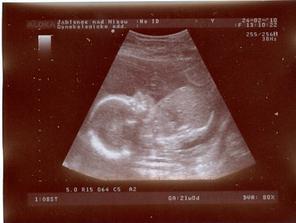

24.2.2010 - Velký utz!!! - ČEKÁME CHLAPEČKA - BUDE TO DAVÍDEK!!!!

Dle utz 21+3tt, vše jak má být, Davídek je naprosto zdravé miminko 🙂